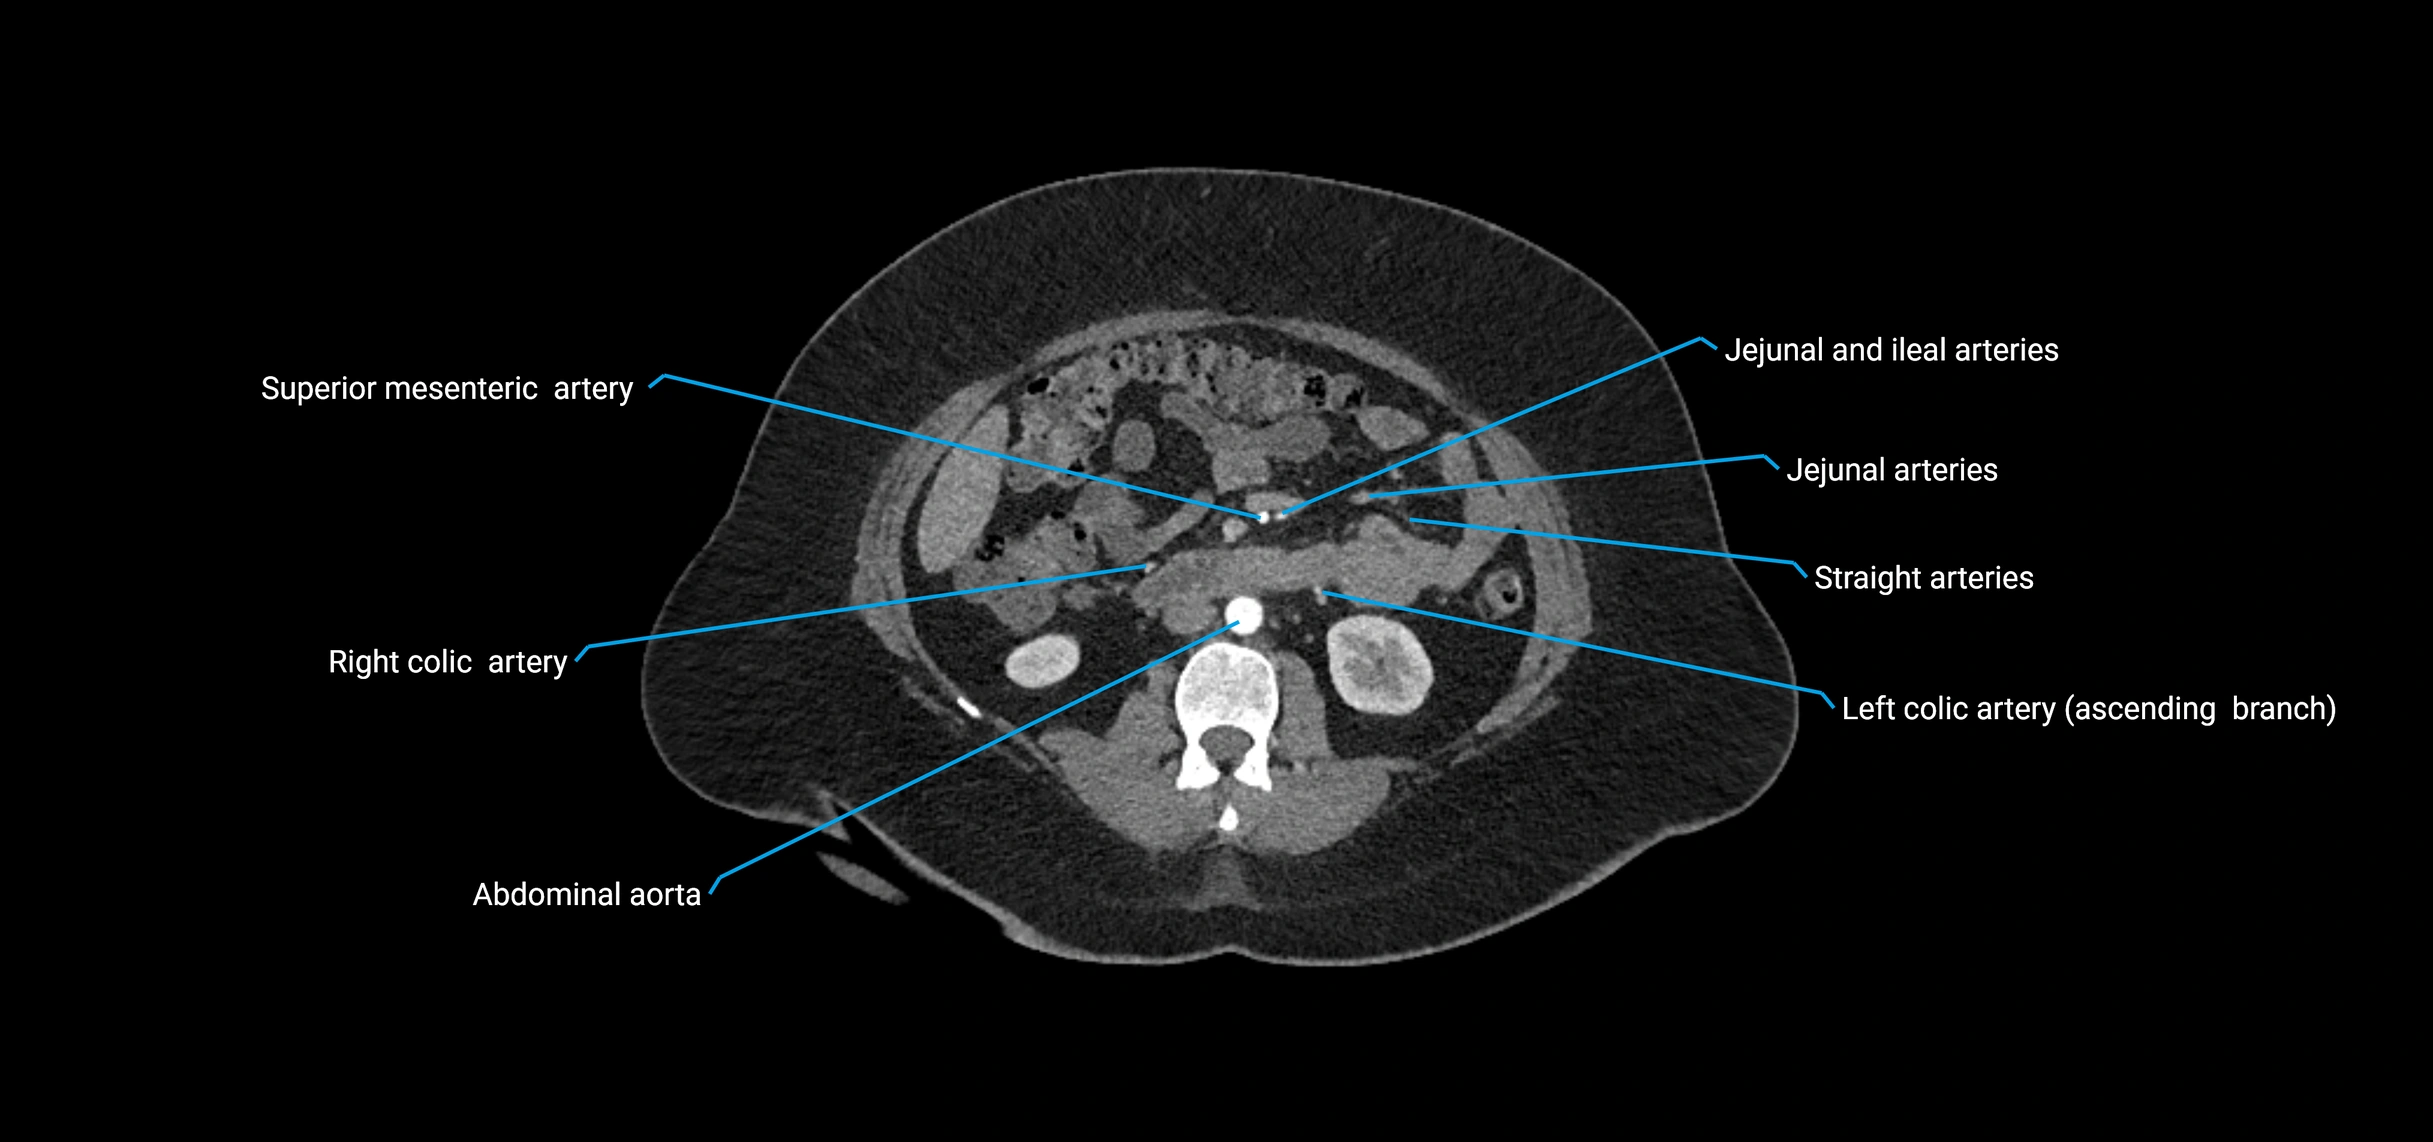

Contrast-enhanced CT (CTA):

• Gold standard for abdominal aortic imaging

• Provides excellent detail of lumen, wall, aneurysm, thrombus, and branch vessels

• Multiplanar and 3D reconstructions help in aneurysm measurement, stent graft planning, and dissection evaluation

• Detects acute rupture, traumatic injury, or occlusion with high sensitivity